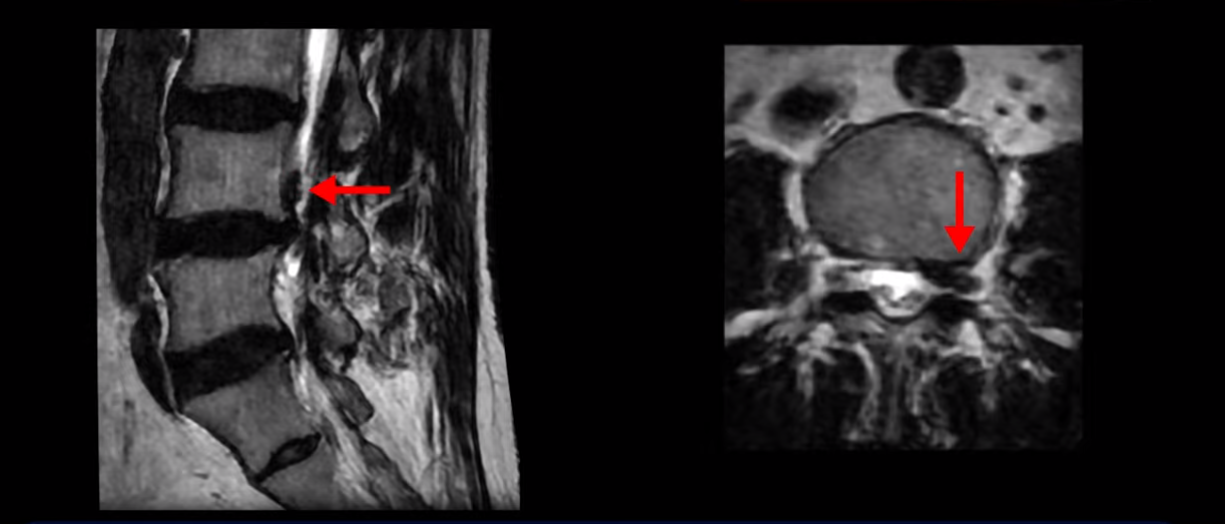

이분 MRI를 보면 허리 세 마디 정도의 퇴행성 디스크가 있고

4번 5번 마디에는 중심성 협착이 있습니다.

후관절과 황색인대가 두꺼워져 있어서 척추관이 좁아져 있습니다.

하지만 이분의 갑작스러운 통증을 일으키는 원인은 4번 5번에 발생한 디스크 파열입니다.

이분은 왼쪽 무릎 아래로 본인 표현으로는 다리를 잘라 버리고 싶다고 할 정도의 심한 통증이 있는데 보통 이런 표현은 디스크 파열이 발생했을 때 많이 사용하는 표현입니다. 이분 4번 5번 디스크를 자세히 보면 왼쪽으로 파열되어 밀려 올라간 디스크 수핵을 볼 수 있습니다.

옆에서도 보이지만 단면에서도 왼쪽으로 심하게 밀려나온 수핵이 잘 보입니다.